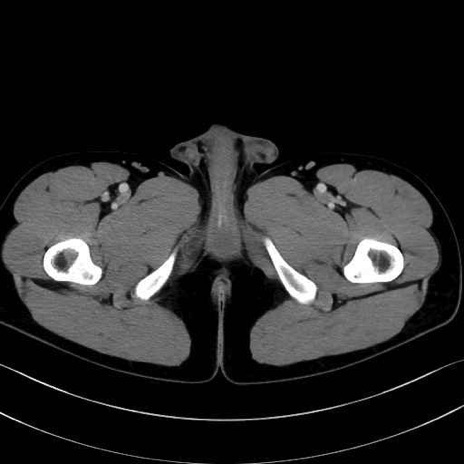

精嚢(seminal vesicle)のCT画像における解剖

症例

【症例】20歳代 男性 スクリーニング